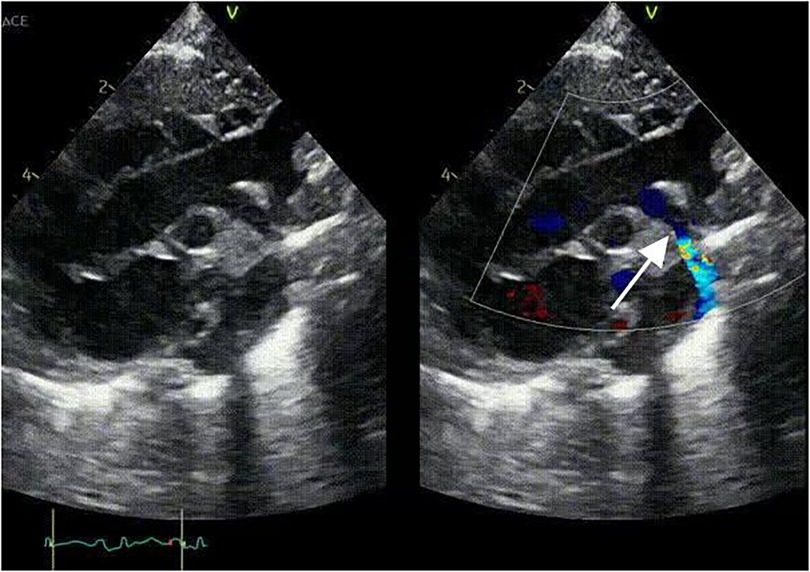

Imaging studies included a chest x-ray showing cardiomegaly and pulmonary congestion, followed by echocardiography, which identified a persistent fifth aortic arch (PFAA) with coarctation (narrowest diameter: 5 mm), an interrupted fourth aortic arch (Figure 1). Color Doppler demonstrating turbulent flow at the coarctation site (peak velocity: 4.1 m/s) (Figure 2). A patent ductus arteriosus (PDA; 3 mm) located between the proximal descending aorta and the pulmonary artery bifurcation, and an atrial septal defect (ASD; 6 × 8 mm), accompanied by reduced left ventricular systolic function (ejection fraction: 49%). Cardiac CT (Figures 3, 4) further confirmed the anatomical details, including a 12 mm gap in the fourth aortic arch and the PFAA's aberrant course.

Ultrasound image showing two views of the heart. The left view displays a grayscale image, while the right view includes color Doppler highlighting blood flow with red and blue areas. An arrow points to a specific section in the right image.

Figure 1. 2D-TTE: persistent fifth aortic arch associated with stenosis (indicated by arrows) and an interrupted fourth aortic arch.